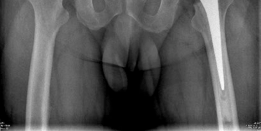

Standard preoperative radiographs included an anteroposterior (AP) pelvis centered over the symphysis pubis with 15 degrees of internal rotation of the lower extremities to profile the femoral necks, alongside true lateral and Dunn lateral views of both hips.

The AP Pelvis radiograph demonstrated severe, bilateral tricompartmental joint space narrowing. The left hip exhibited complete obliteration of the superior and axial joint spaces with bone-on-bone articulation. Subchondral sclerosis was prominent bilaterally, accompanied by marginal osteophyte formation at the femoral head-neck junction and the acetabular rim. Large subchondral cysts (geodes) were visible in the superior weight-bearing dome of the left acetabulum.

The lateral view of the left hip confirmed the loss of sphericity of the femoral head, extensive anterior and posterior osteophytosis, and severe joint space collapse.

The lateral view of the right hip demonstrated similar but slightly less advanced degenerative changes, with marked loss of anterior joint space and reactive subchondral bone formation.